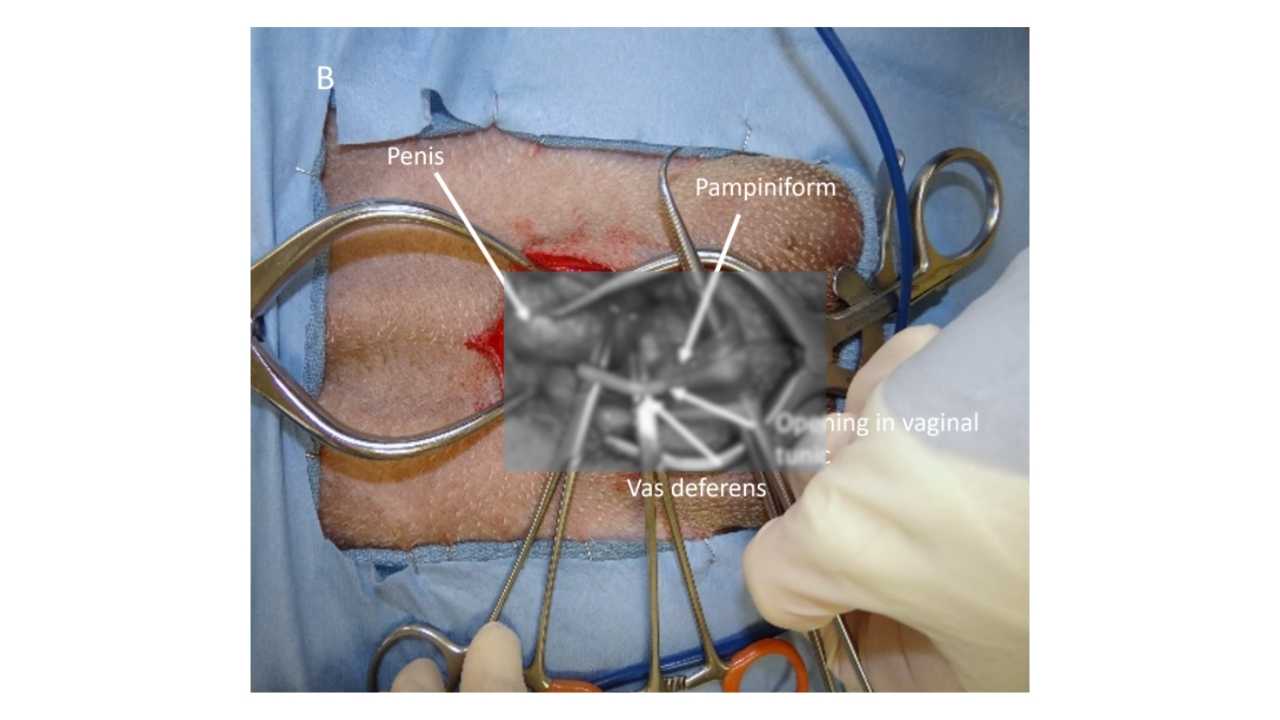

A vasectomy removes the vas deferens but leaves the testicles intact. Testosterone production continues.

This can preserve joint strength, muscle mass, and long-term health while still preventing reproduction.

Ovary-Sparing Surgery for Female Dogs

This involves removing the uterus and cervix while leaving the ovaries intact.

Estrogen continues to be produced, which helps protect bones, joints, and overall health.

These procedures are not complex and more practitioners are now offering them.